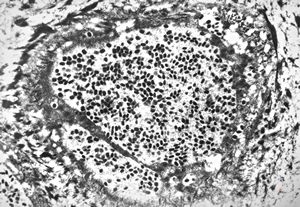

F, 1m. | sepsis - mycotic dermal lesions

M, 57y. | dermal mycotic lesion

M, 57y. | dermal mycotic lesion … toluidine-blue stained semithin section